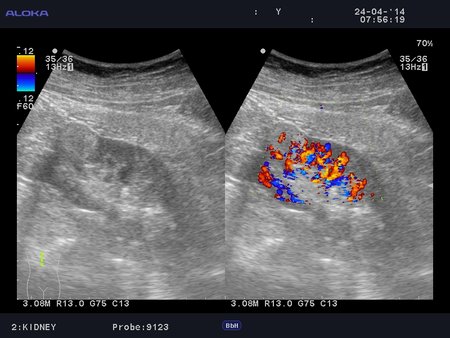

Онкоцитома почки - УЗИ

Женщина 76 лет. Жалоб не предъявляет.

Renal oncocytoma